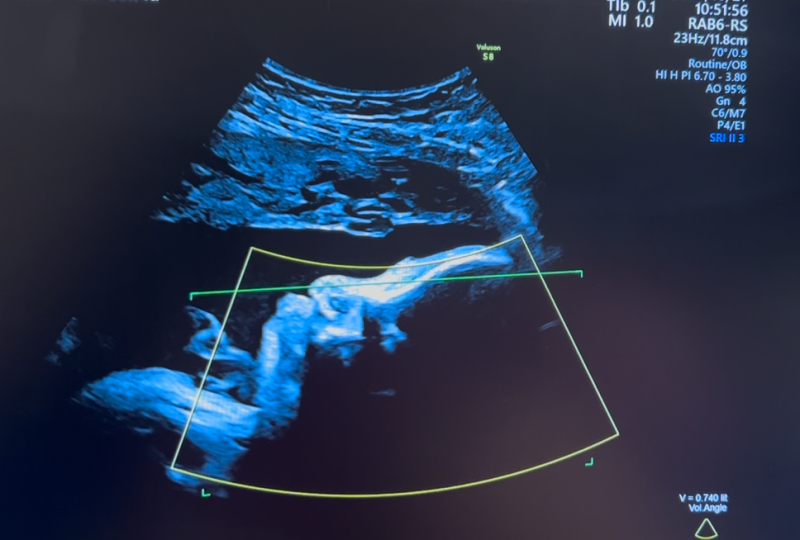

妊婦健診で4Dのエコー写真を撮って頂けるのですが、

顔の特徴がダウン症の特徴と同じのような感じがして

不安です。鼻は低いし目がつり目?のような浮腫んでるような…。

※写真は28週、35週、32週の順です。